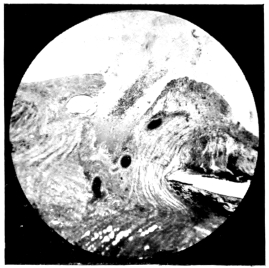

10.

LENS DISLOCATED BETWEEN CILIARY BODY AND SCLERA

curly bracket span

38

11.

NUCLEUS OF CATARACT FREELY MOVABLE BETWEEN THE AQUEOUS AND VITREOUS CHAMBERS

12.

LENS IMPACTED IN ANGLE OF ANTERIOR CHAMBER

13.

CAPSULE OF MORGAGNIAN CATARACT IMPACTED IN ANGLE OF ANTERIOR CHAMBER

14.

LENS FLOATING FREE IN VITREOUS CHAMBER

15.

LENS LIGHTLY IMPRISONED IN EXUDATE INTO VITREOUS CAVITY